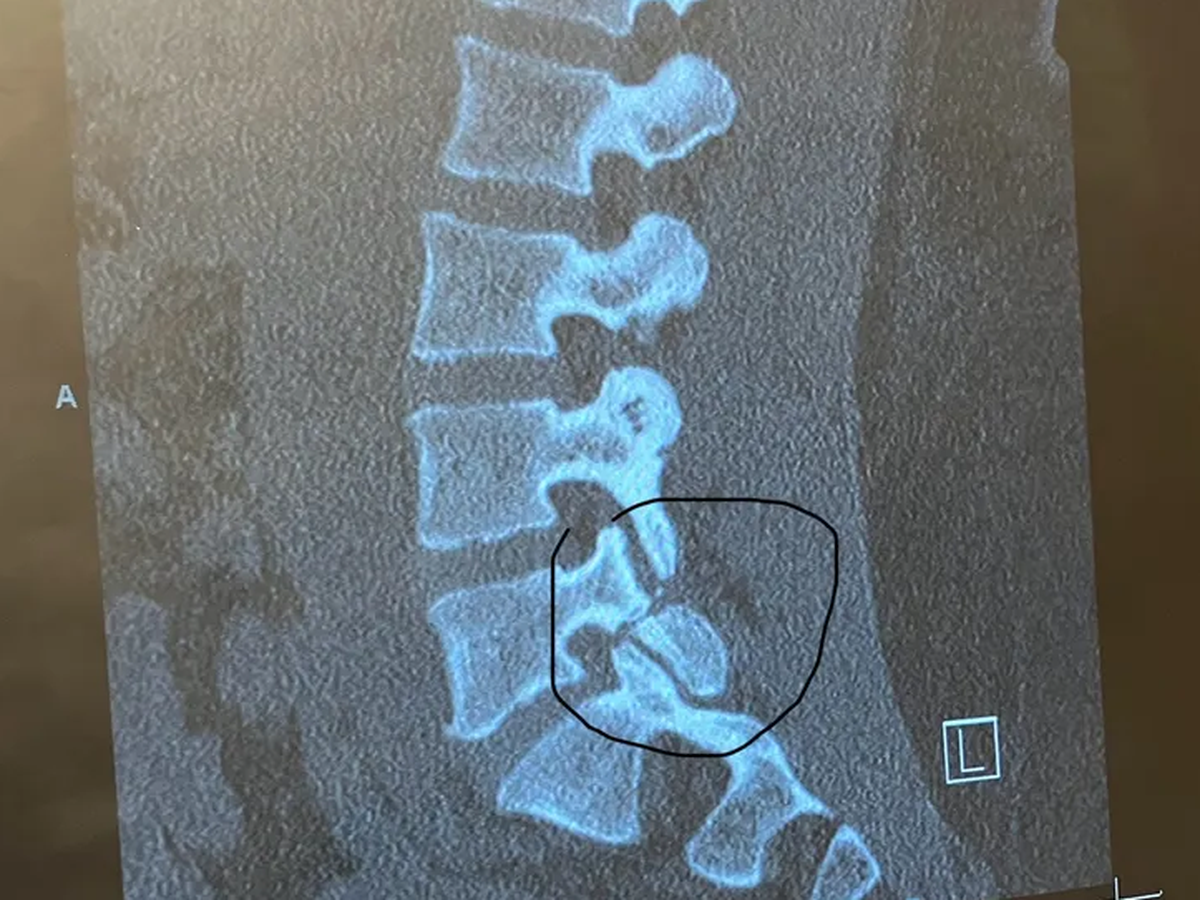

My name is Tradara. I am in my early 30s and have recently been scheduled for an L5-S1 Posterior Lumbar Interbody Fusion. In other words, MAJOR back surgery. I will undergo emergency back surgery—a decision that couldn’t be delayed due to the severity of my condition. While the surgery is necessary to protect my long-term health, the aftermath will leave me in an incredibly difficult place physically and financially.